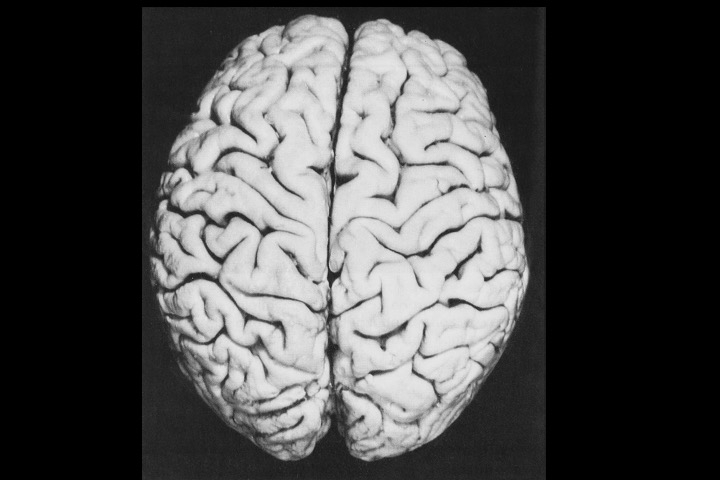

O Prof. Emérito da UFRJ Dr. Adalmir Morterá Dantas está disponibilizando através de nosso website e de nosso canal youtube (cursobom) o Museu de Neuroanatomia, no intuito de promover esta área de conhecimento junto aos estudantes de Medicina.

As figuras são apresentadas em 4 vídeos no youtube e podem ser obtidas via download clicando-se na figura em questão.